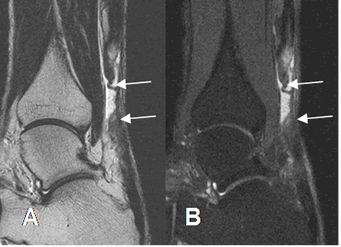

Fig 87. Ruptura no insercional del aquiles.

A: RM sagital en T2 y B: RM sagital en STIR. Ruptura completa del aquiles en la zona crítica, con separación de los extremos.